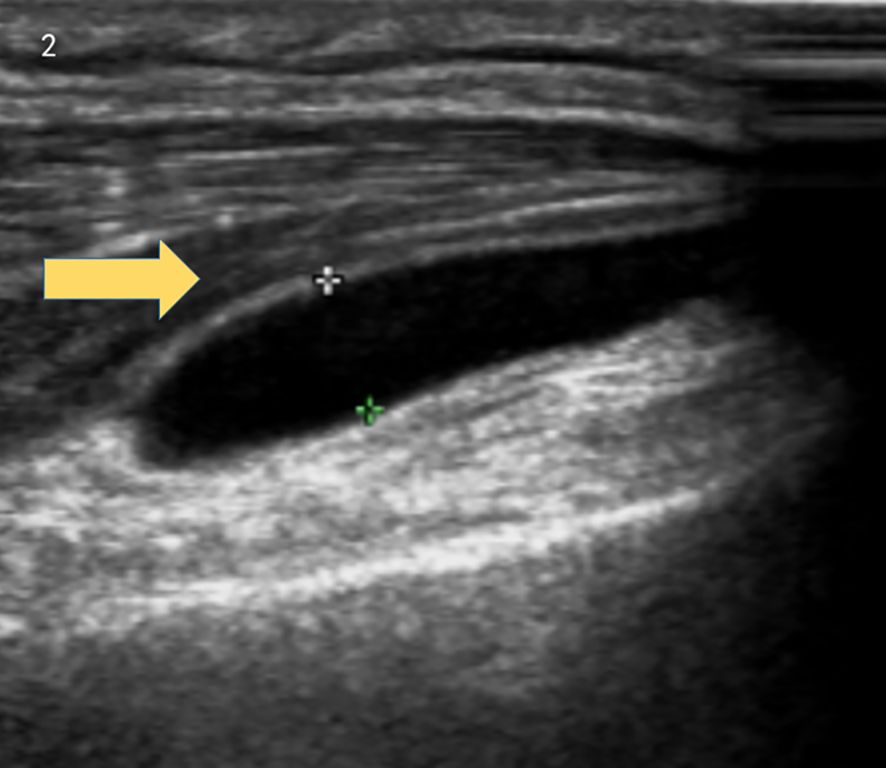

Brain MRI indicated multiple small ischemic lesions and a softening lesion in the left frontal lobe (Figures 1A, B). Imaging studies included ultrasound, revealing right lateral epicondylitis and right knee effusion (Figure 2). Echocardiography identified severe pulmonary hypertension and widened pulmonary arteries with findings consistent with congenital heart disease following ventricular septal defect repair.

Ultrasound image showing the cross-section of a blood vessel with a yellow arrow pointing to a dark hollow area, representing the vessel’s lumen. Dense surrounding tissues appear as layered patterns.

Figure 2. Ultrasound revealed right lateral epicondylitis and right knee joint effusion.